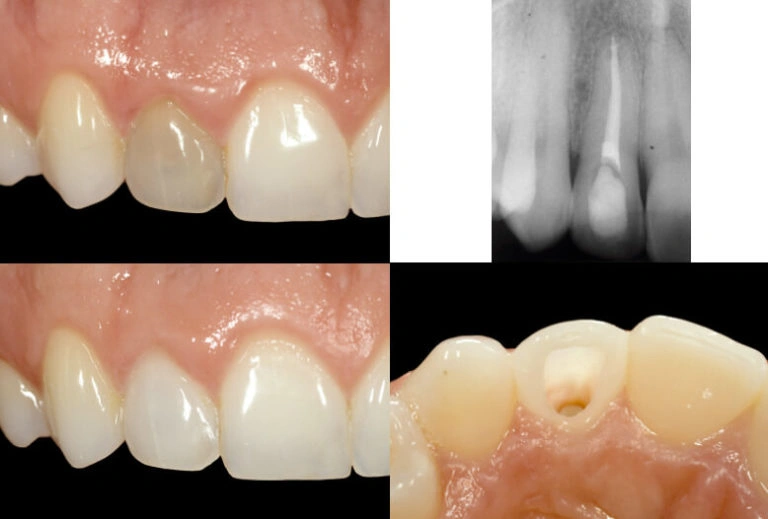

USING INTERNAL BLEACHING TO IMPROVE THE APPEARANCE OF A DARK FRONT TOOTH:

- We place a special material inside the tooth to bleach it from the inside.

- We place a temporary filling on top of the material

- You then walk around with it for 1-2 weeks (hence the name walking bleach).

- When the tooth has achieved a similar color to the neighboring teeth, we remove the bleaching material and place a very white filling to keep the tooth white for as long as possible.

Before and After